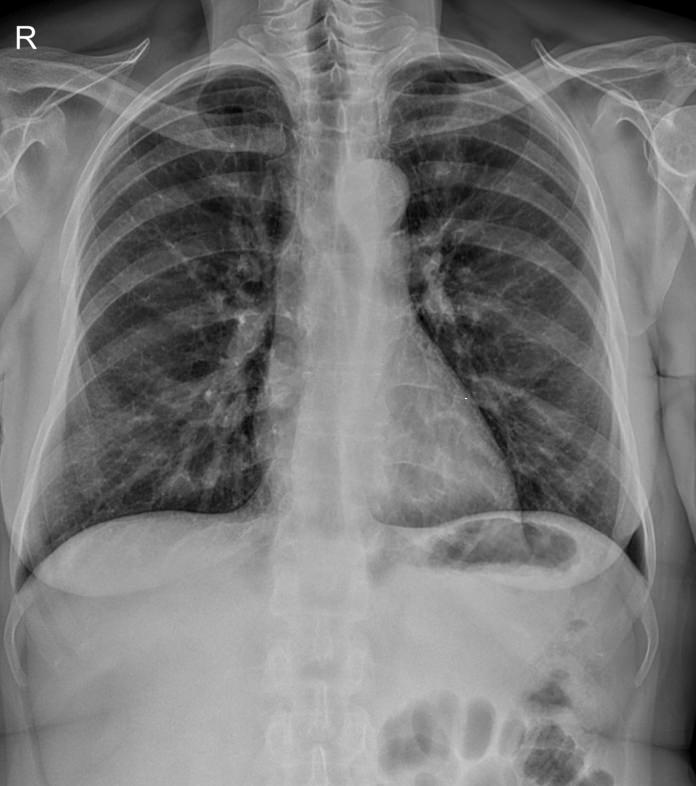

В качестве основного метода исследования при патологии ребер назначают рентгенодиагностику. Это простой и доступный способ узнать состояние костной ткани изнутри, не нарушая целостности кожных покровов. минимальная доза излучения современных рентгеновских аппаратов делает рентгенографию безопасной.

Что покажет рентген ребер (прицельно)

На рентгенограмме будут видны:

• Перелом и его локализация;

• Отек, отломки и осколки кости и инородные тела в мягких тканях;

• При рентгене верхних ребер ― возможные повреждения тканей легких, трахеи, пищевода;

• При обследовании нижних ребер ― повреждение тканей и органов верхней части живота: печени, селезенки, почек, диафрагмы.